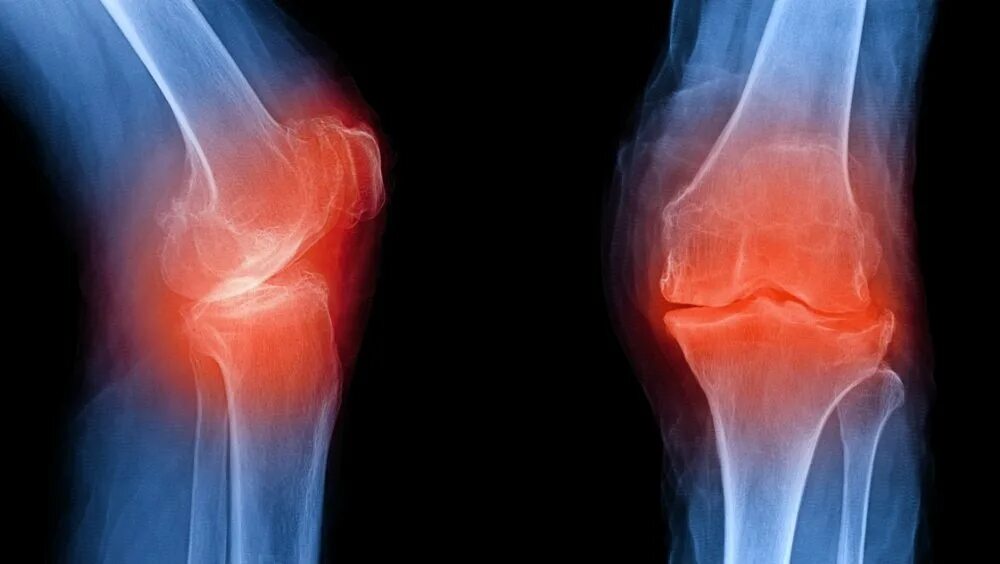

Явления остеоартроза